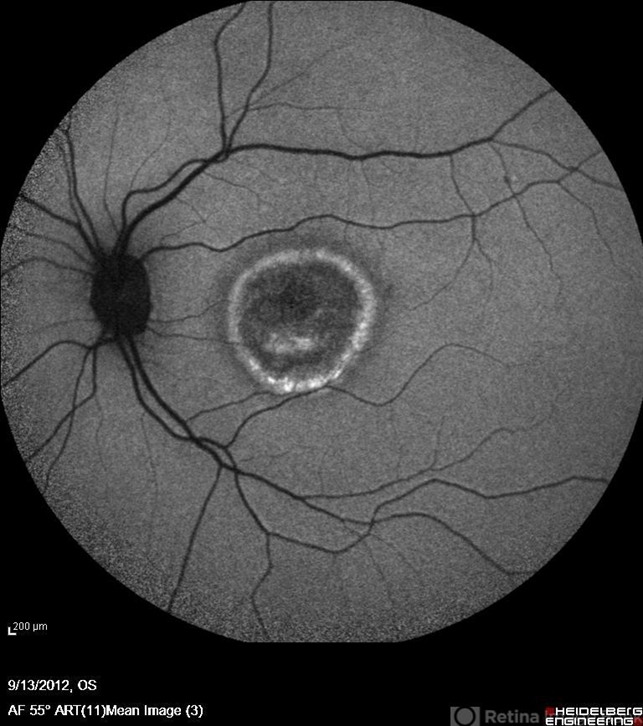

- Best disease, autofluorescence imaging

- Soodabeh Fooladin, Negah Eye Center, Tehran

- Heidelberg Spectralis

- Autofluorescence Imaging of the left eye of a 49-year-old man with decreased VA due to advanced Best disease.